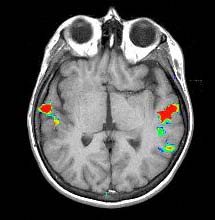

T1 weighted MRI

Transverse image at the level of the planum temporale. The left hemisphere is seen in the right side (radiological convention). The subject's task was listening to a story.The red bubble seen on the left side corresponds to areas related to complex semantic processing.

Functional MRI is based on small signal changes that result from the following cascade of events. A task elicits activation in one or several brain areas. These areas increase their metabolic demands, suffer vasodilatation, and alter their levels of deoxyhemoglobin and oxyhemoglobin. Since deoxyhemoglobin is a paramagnetic molecule, it influences the phase of local proton-spins, altering the source signal that is converted into images. Therefore, the image is a representation of local changes of levels of deoxyhemoglobin, related to the brain region performing a task.